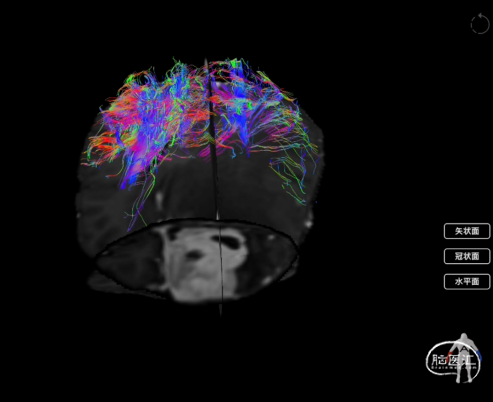

术后使用Nura Surigical脑网络重建分析显示:中央执行网络及皮质脊髓束较术前变化不大

图4:术前术后重建的中央执行网络对比(左侧为术前;右侧为术后)

图5:术前术后重建的皮质脊髓束对比(左侧为术前;右侧为术后)